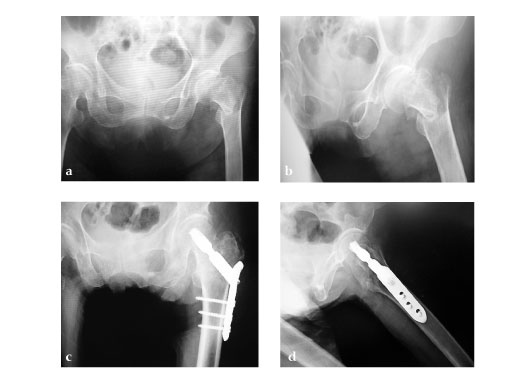

80-year-old female.

Case provided by Takefumi Kuroki, Fukuoka, JP